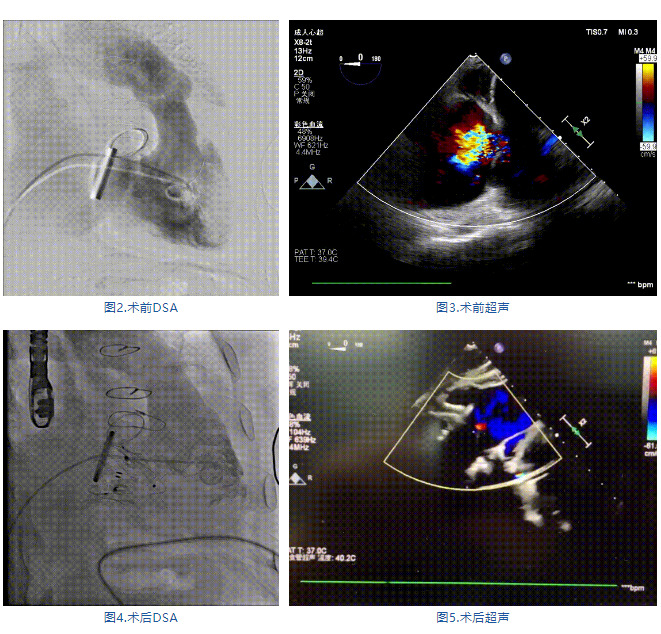

手術(shù)在全麻狀態(tài)下進(jìn)行,郭惠明教授團(tuán)隊(duì)采用經(jīng)右側(cè)頸靜脈入路的方式送入輸送器進(jìn)入體內(nèi),并在TEE和DSA的指引下進(jìn)行。在輸送器進(jìn)入右室后釋放室間隔錨定裝置,旋轉(zhuǎn)輸送器,使得錨定裝置對準(zhǔn)室間隔面;而后釋放前瓣夾持件,確定夾持件位于右室側(cè)釋放LuX-Valve Plus人工瓣膜盤片,再使用DSA和超聲確認(rèn)盤片是否位于右房側(cè),同時調(diào)整瓣膜的同軸性。緊接著在DSA和超聲的監(jiān)視下調(diào)整室間隔錨定件貼合室間隔,釋放室間隔錨定裝置。再次確認(rèn)瓣膜的穩(wěn)定性和同軸性后,將輸送器撤出體內(nèi),最終完成LuX-Valve Plus人工瓣膜植入(圖2-5),手術(shù)獲得圓滿成功?;颊咴谑中g(shù)室即刻拔除氣管插管,術(shù)后超聲提示LuX-Valve Plus人工三尖瓣瓣膜同軸性良好,瓣架固定牢靠,無反流和瓣周漏。